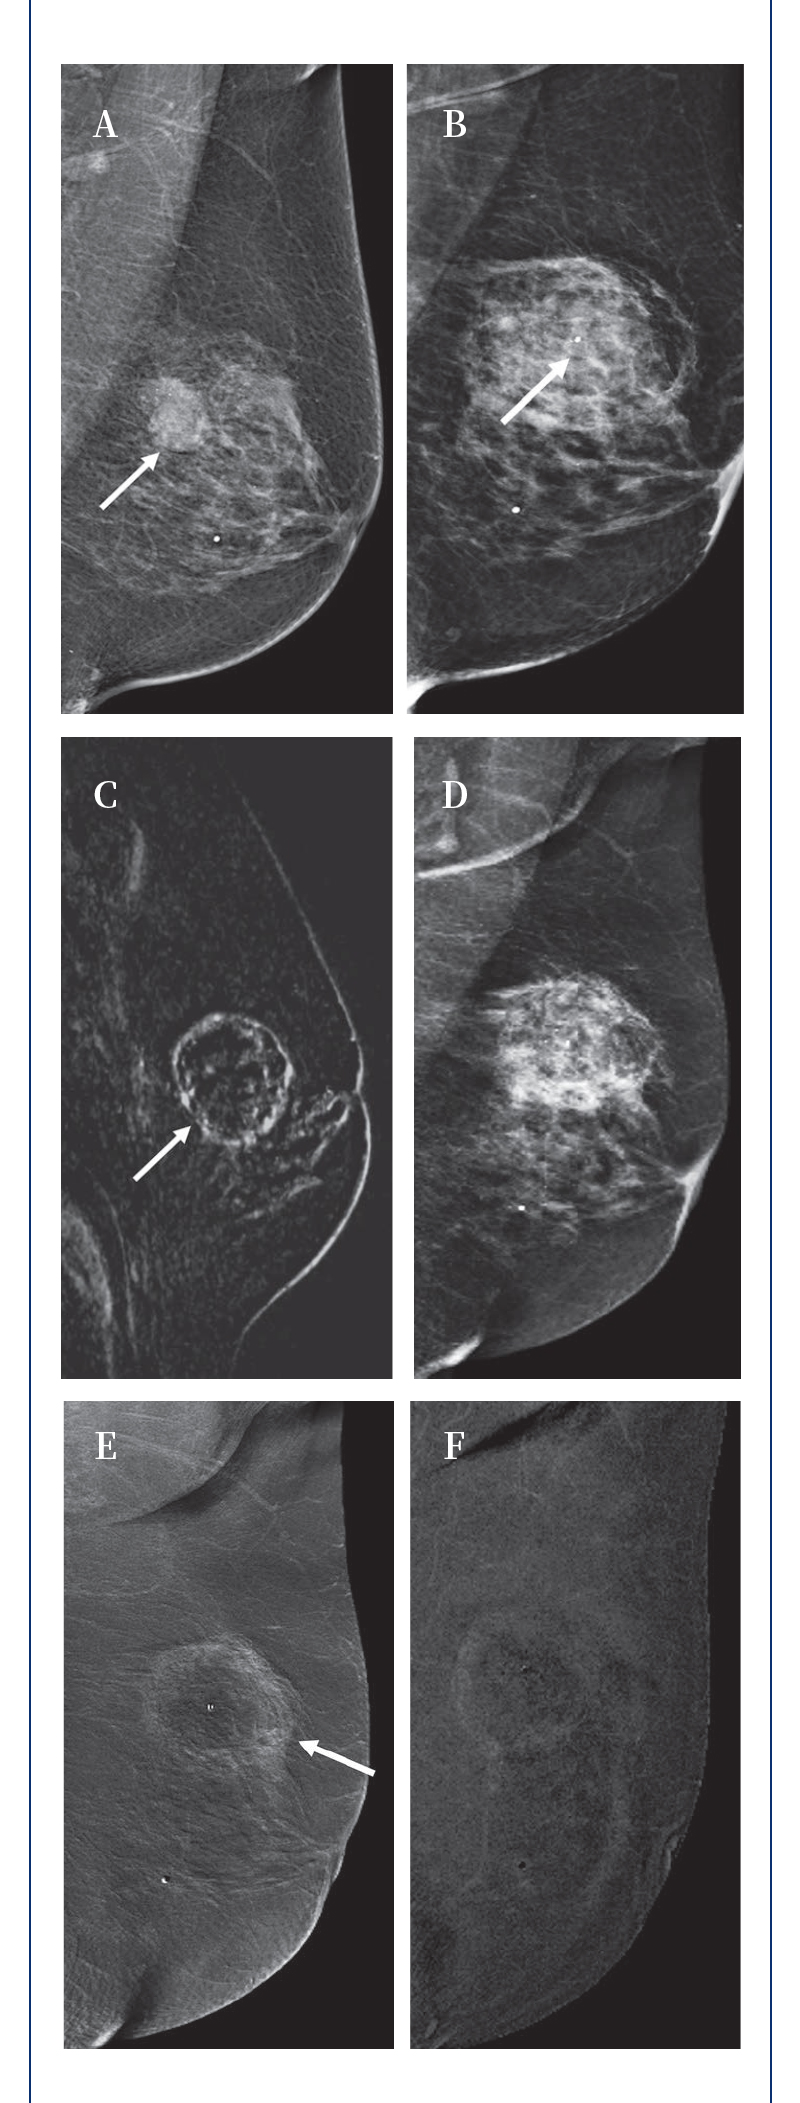

【HYGEA·科研資訊】乳腺癌冷凍消融